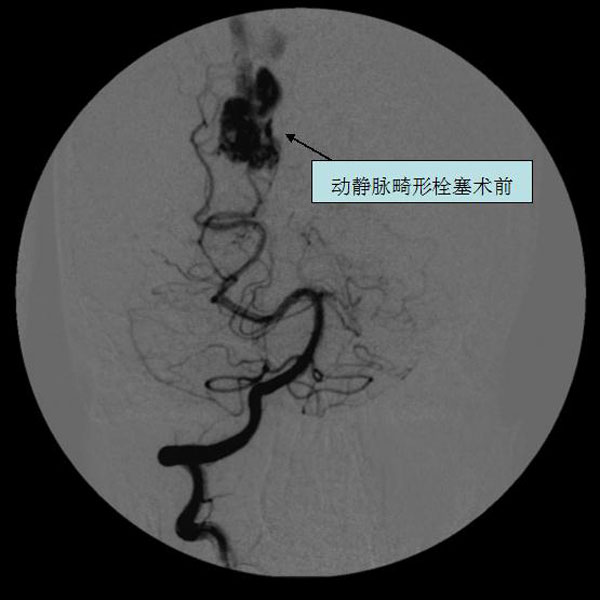

脑血管畸形栓塞术前

脑血管畸形栓塞术后